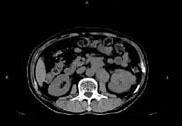

问题 男,65岁,左腰部隐痛不适2个月,CT平扫+增强如图所示,下列说法正确的是 ( )

选项 A、考虑为左肾癌伴肾门淋巴结转移 B、增强扫描可见左肾局部隆起左肾内的病灶强化方式相同 C、腹腔内未见积液,所示骨质亦未见破坏 D、平扫时可见左肾局部隆起,腹主动脉旁、肾门部有等密度的块影

答案 ABCD